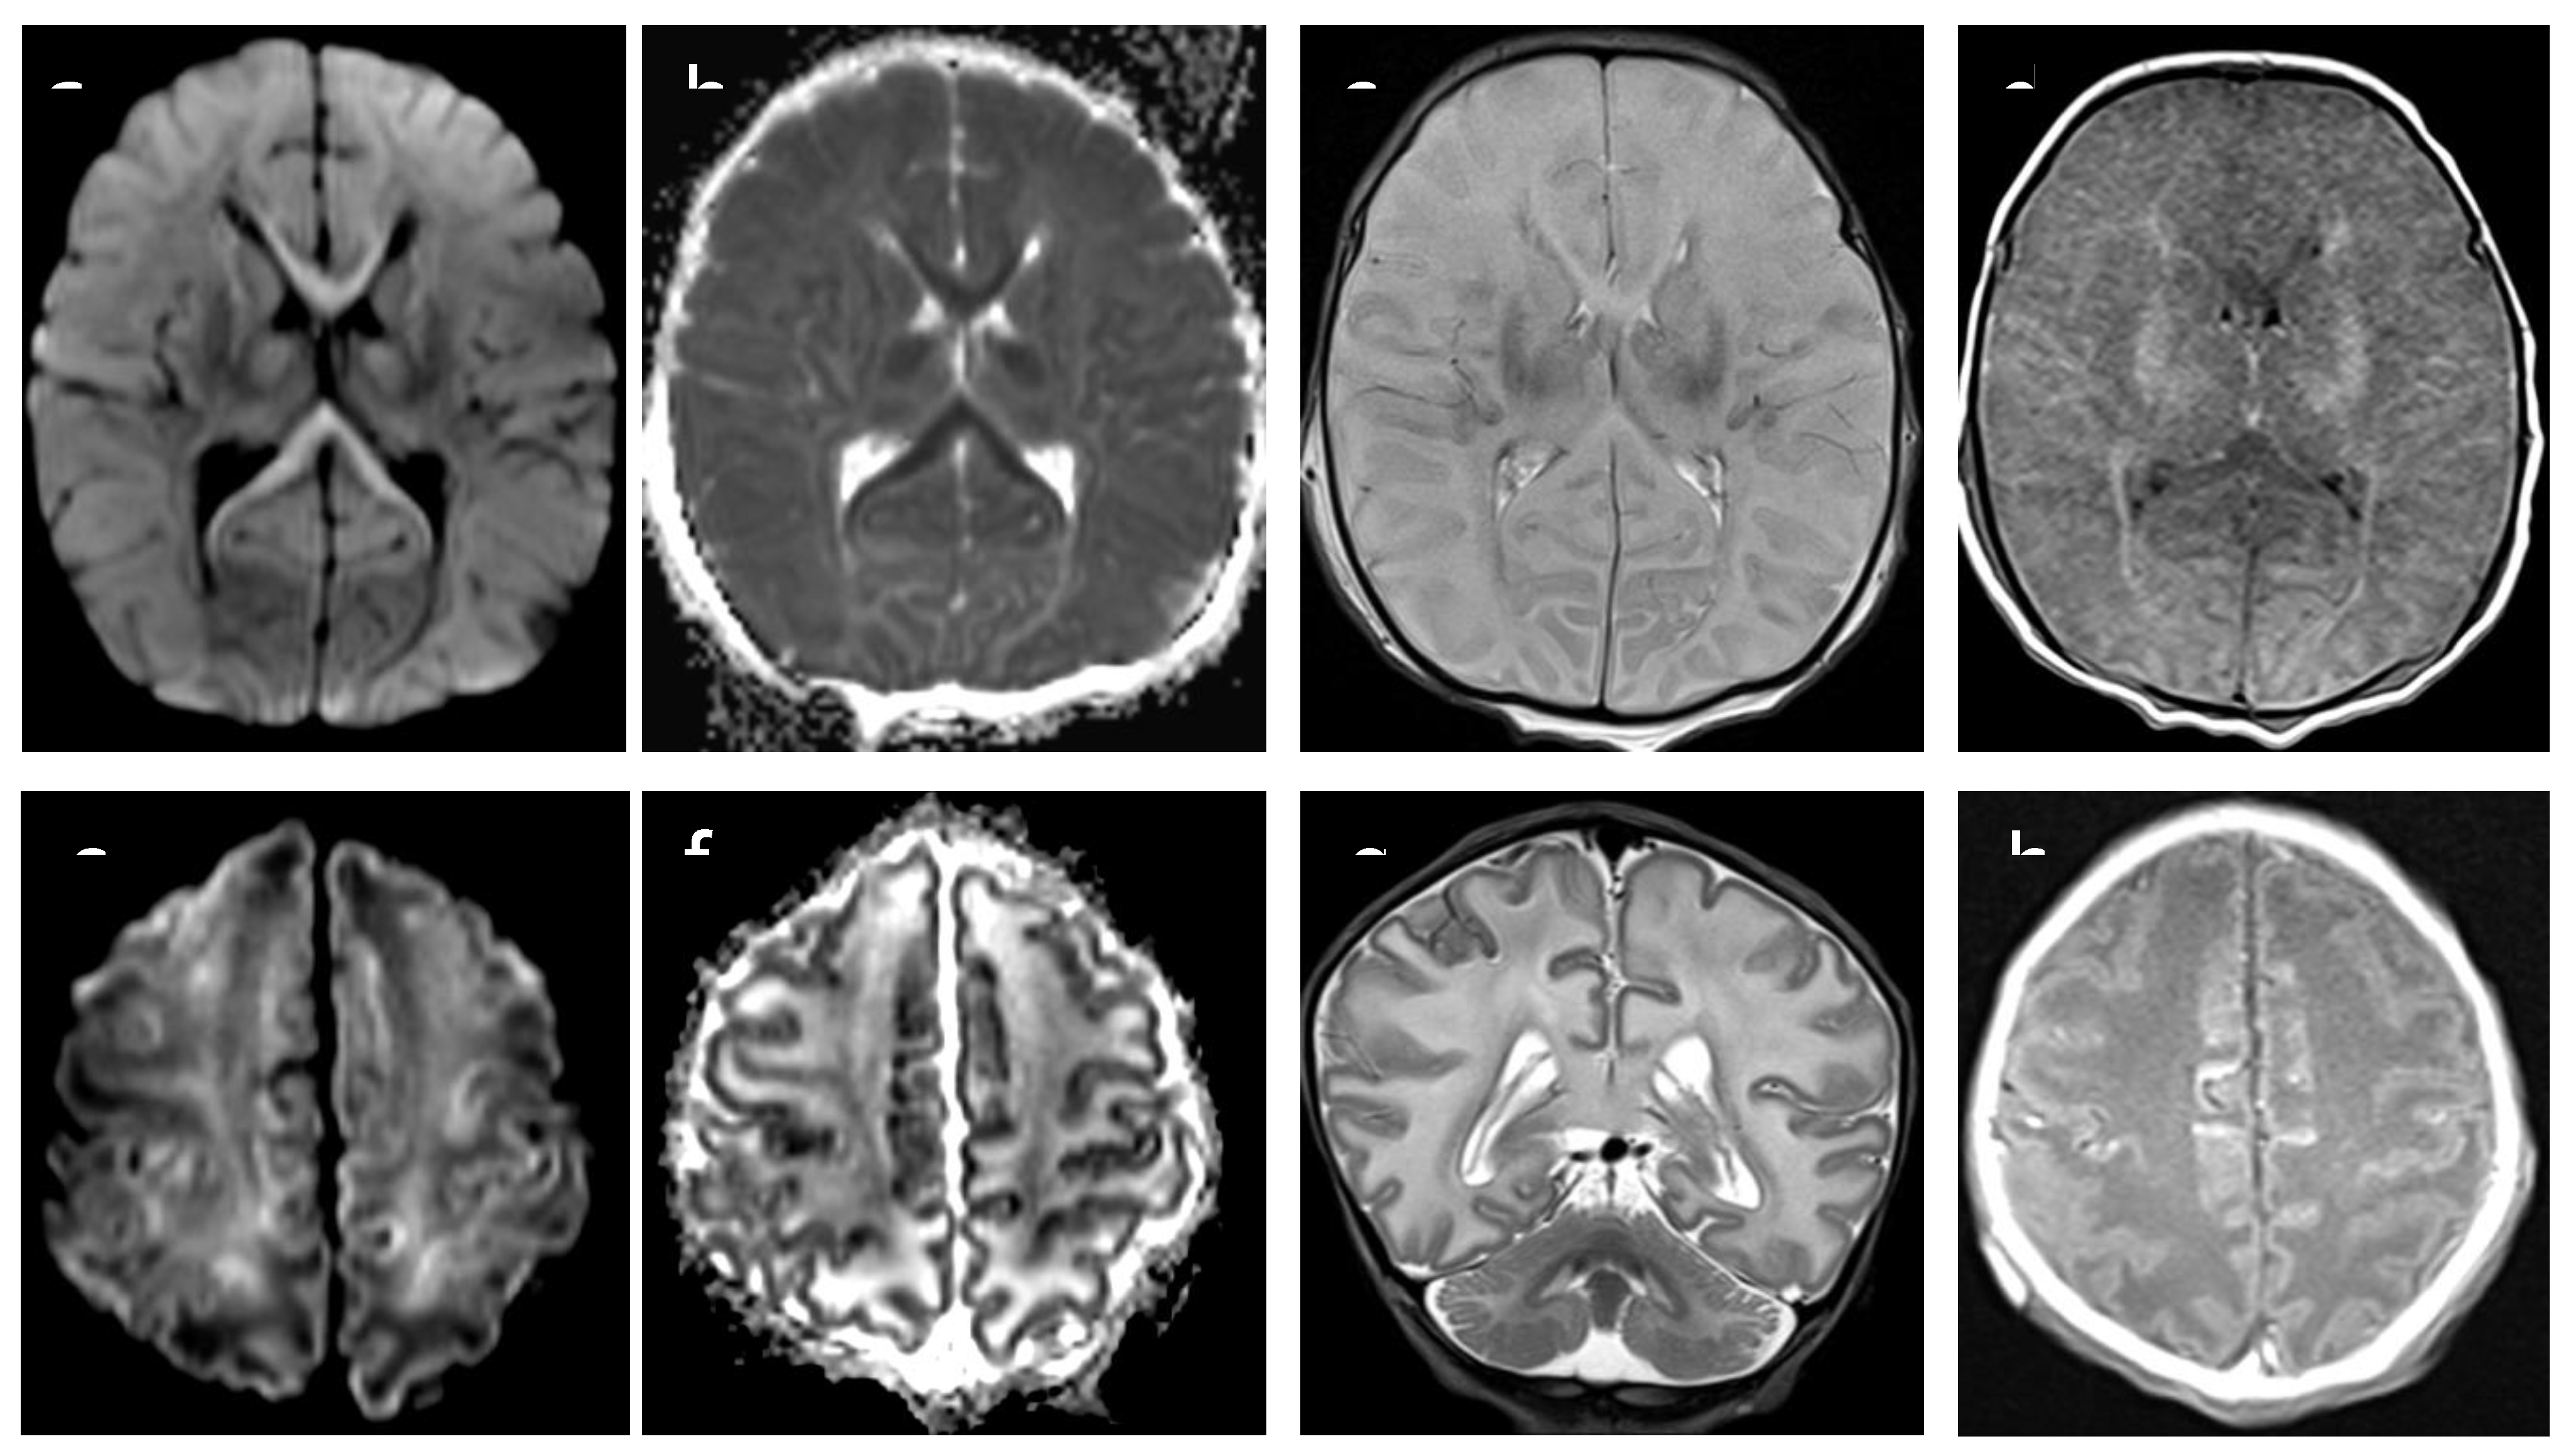

Figure 1. MRI axial DWI/ADC images (a,b,e,f) show restricted diffusion in basal ganglia, cortex and corpus callosum in asphyxiated neonate. T2 axial and coronal images (c,g) show cortical edema, resulting in marked loss of normal cortical/white matter contrast ; hyperintensity in T1 axial image (d,h) indicate bilateral injury of basal ganglia and cortical precentral gyrus Acute and severe hypoxia in term infants results in damage to the gray matter, especially the basal ganglia with Barckovich score 4 (BG/W).

Based on brain MRI performed between 7 and 10 days of life, we selected 10 neonates who had been admitted to our NICU to undergo TH because of moderate to severe perinatal asphyxia. Five of those neonates had severe MRI examination, with abnormal signal in entire cortex and basal nuclei (“cases”) and five had completely normal MRI examination (“controls”) (Figure 1 and Figure 2). During TH, infants were cooled to maintain a core temperature at 33.5°C (with accepted variation between 33°C and 34 °C) for 72 hours, followed by rewarming by 0.5°C/hour over 6 hours. Brain MRI was performed at 7-10 days of life, after the rewarming phase. MRI protocol (3-T Skyra, Siemens, Erlagen, Germany) included: axial T1 SE, sagittal T1 TIRM, axial and coronal T2 TSE and DWI with a single-shot echo-planar sequence. Additional sequences were axial T2 GRE and axial T2 FLAIR. Brain MRI pathological lesions were classified according to the Barkovich score (12).